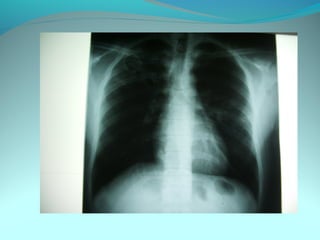

Image radiologique bilaterale

A droite : clarté sous claviculaire et axilaire droite arrondie de 3 cm de

diam entourée d une paroi de 4mm d’épaisseur

Le 1/3 sup du poumon droit est le siege d’opacité nodulaire avec

quelque clarté

A gauche: le 1/3 moyen est le siege d’opacité nodulaire et de clarté de

taille variable

DIAGNOSTIC:

Tuberculose pulmonaire bilaterale cavitaire